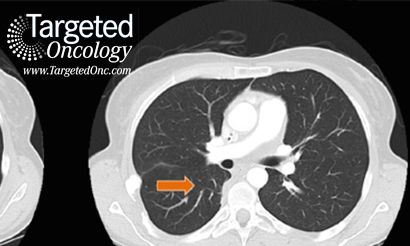

Metastatic disease accounts for the vast majority of cancer-related deaths. Ensuring a definitive diagnosis and the most effective treatment in a timely fashion is essential for extending life expectancy.